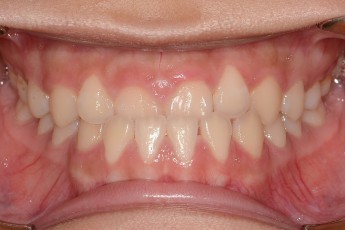

BEFORE & AFTER

- 반대교합교정